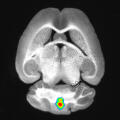

In atherosclerosis, plaque deposits (yellow) build up in arterial walls, which, upon rupture, can lead to heart attack or stroke. CiM scientists investigate inflammatory processes pivotal to this rupture. Planar illumination fluorescence microscopy© Jan Prodöhl, Lisa Honold, Friedemann Kiefer, Michael Schäfers